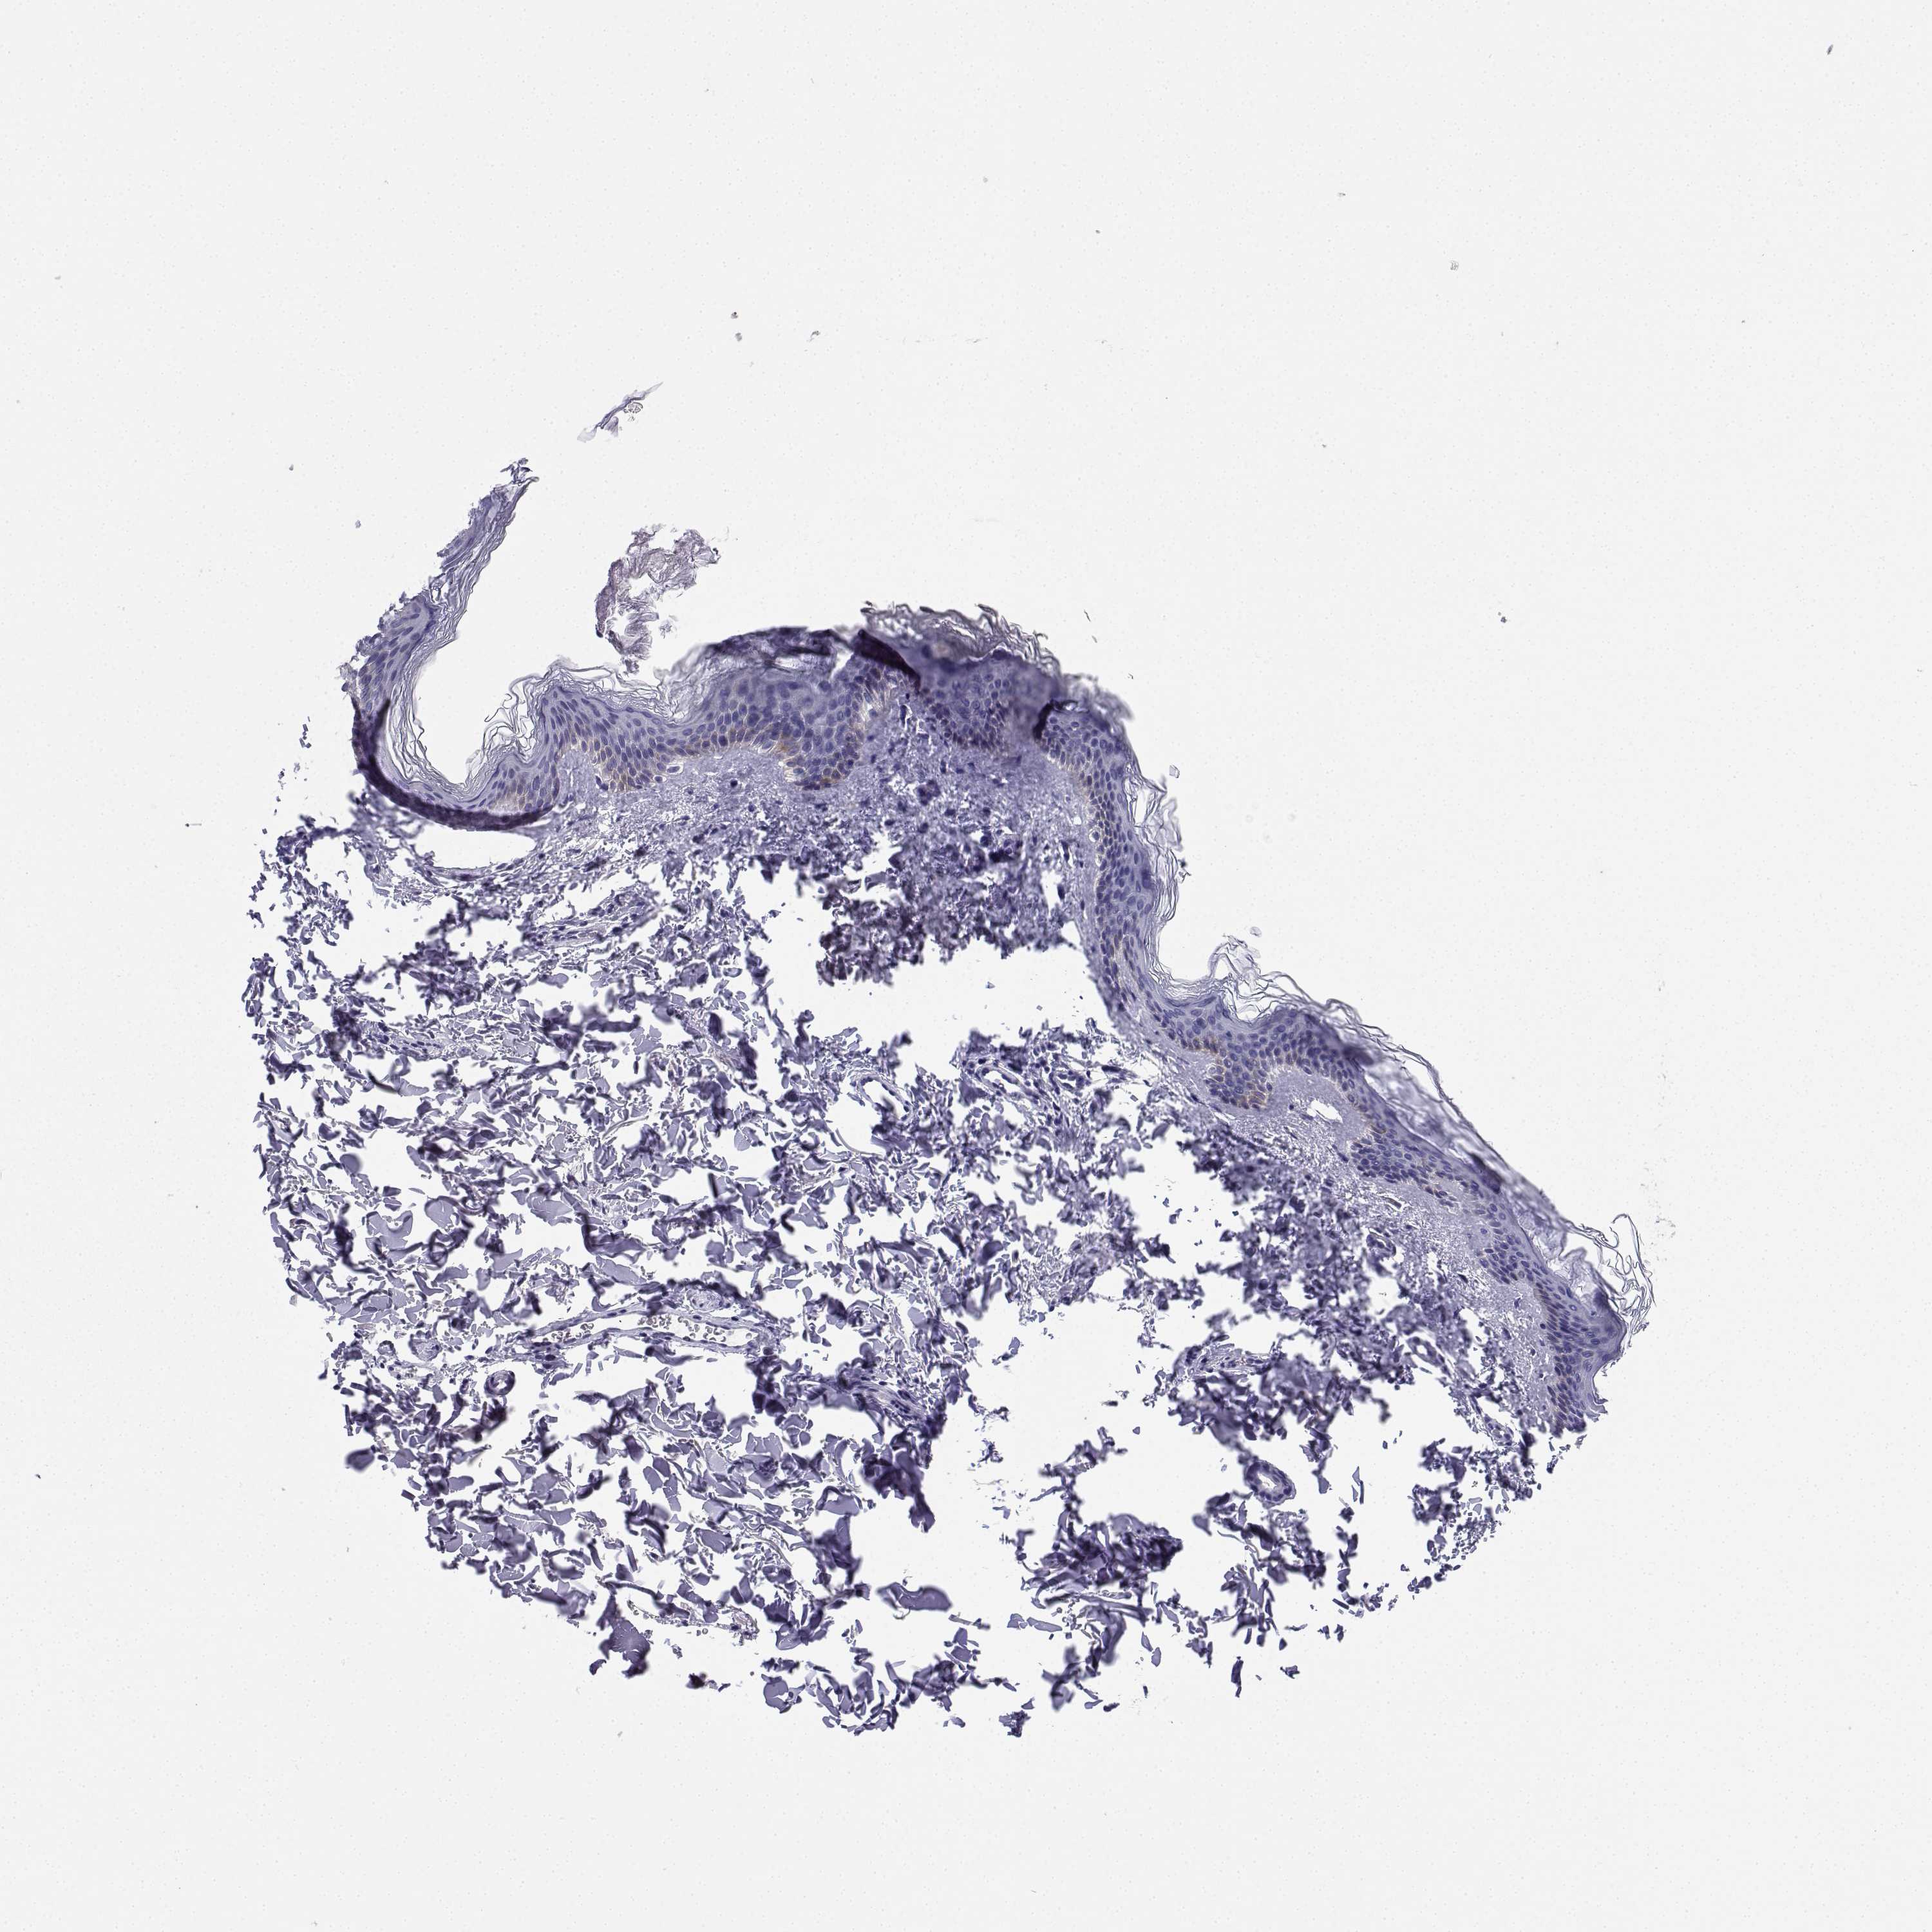

SKIN CANCER - Protein expressioni

A mouse-over function shows sample information and annotation data. Click on an image to view it in a full screen mode. Samples can be filtered based on level of antibody staining by selecting one or several of the following categories: high, medium, low and not detected. The assay and annotation is described here.

Antibody stainingi

Antibody staining in the annotated cell types in the current human tissue is reported as not detected, low, medium, or high, based on conventional immunohistochemistry profiling in selected tissues. This score is based on the combination of the staining intensity and fraction of stained cells.

Each image is clickable and will lead to virtual microscopy that enables deeper exploration of all samples and also displays staining intensity scores, fraction scores and subcellular localization as well as patient and tissue information for each sample.

Antibody HPA042283

Basal cell carcinoma

Squamous cell carcinoma, NOS